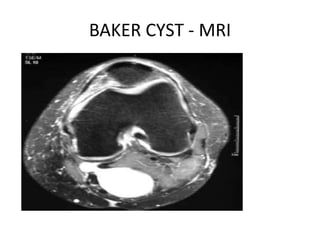

POPLITEAL (BAKER) CYST

• Presents with posteroinferior knee pain

• Develops posteriorly and inferiorly to the knee

as a distention of a local bursa

• The cyst frequently communicates with the

knee (especially in adults), and associated

intra-articular pathology is common.

• The cyst may develop as a herniation of the

synovial membrane through the posterior

joint capsule.

• Popliteal venous thrombosis can be confused

with the pain and swelling produced by these

posterior cysts or may exist concomitantly.

• Other potential diagnoses include aneurysms,

vascular tumors, lipoma, and other tumors.

BAKER CYST - MRI

• Treatment - surgical excision